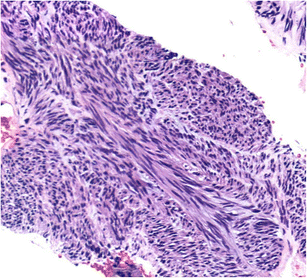

• Gastrointestinal stromal tumors (GISTs) are uncommon intramural tumors of the GI tract. They are most often seen in the stomach and arise from the muscular layers of the visceral wall.

• Advances in endosonography (EUS) and immunohistochemical staining can distinguish these lesions from other intramural and GI tract tumors and are an essential part of the diagnostic and staging workup.

• The advent of EUS-guided fine needle biopsy (FNB) allows for large core tissue acquisition. This has replaced FNA and allowed for histologic analysis of large specimens, increased IHC confirmation, and personalized medicine.

• The cases presented in this report represent pathology-confirmed GISTs diagnosed at a large volume, community, tertiary referral GI oncology program during July 2012 through May 2016. Follow-ups for each patient have discovered no recurrences to date.